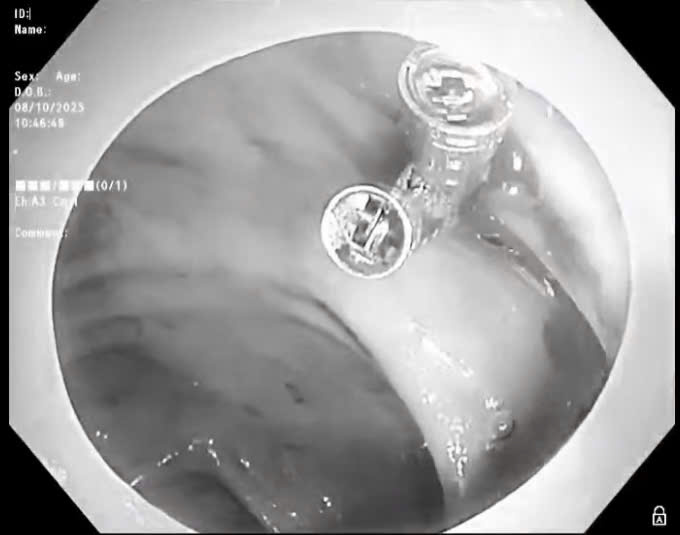

Các bác sĩ xử trí kịp thời ca bệnh sốc giảm thể tích do xuất huyết tiêu hóa.

Sáng ngày 8/10, người bệnh được chỉ định nội soi đại tràng cấp cứu. Qua nội soi, quan sát thấy đại tràng có nhiều cục máu đông, tại vị trí túi thừa đại tràng ngang có điểm mạch, máu tươi chảy thành tia. Bác sỹ nội soi đã thực hiện cầm máu bằng 03 kẹp hemoclip. Sau can thiệp, tình trạng bệnh nhân hiện tại ổn định, đang được tiếp tục điều trị tại bệnh viện.

Theo BSCKI Trịnh Thị Liễu - Trưởng khoa Khám bệnh, là bác sĩ trực tiếp nội soi cho biết: "Chảy máu túi thừa đại tràng là một biến chứng thường gặp trong chảy máu đường tiêu hóa, tỷ lệ khoảng 30-65%. Với trường hợp người bệnh P đang xảy ra tình trạng chảy máu cấp, máu phun thành tia, nếu không được cầm máu, xử lý kịp thời sẽ dẫn đến sốc mất máu, ảnh hưởng nguy kịch đến tính mạng."